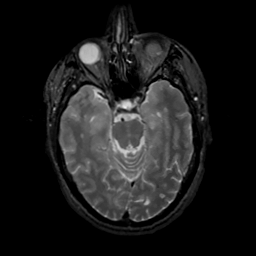

MR Study #13, May 19, 1991 -- Slice #18